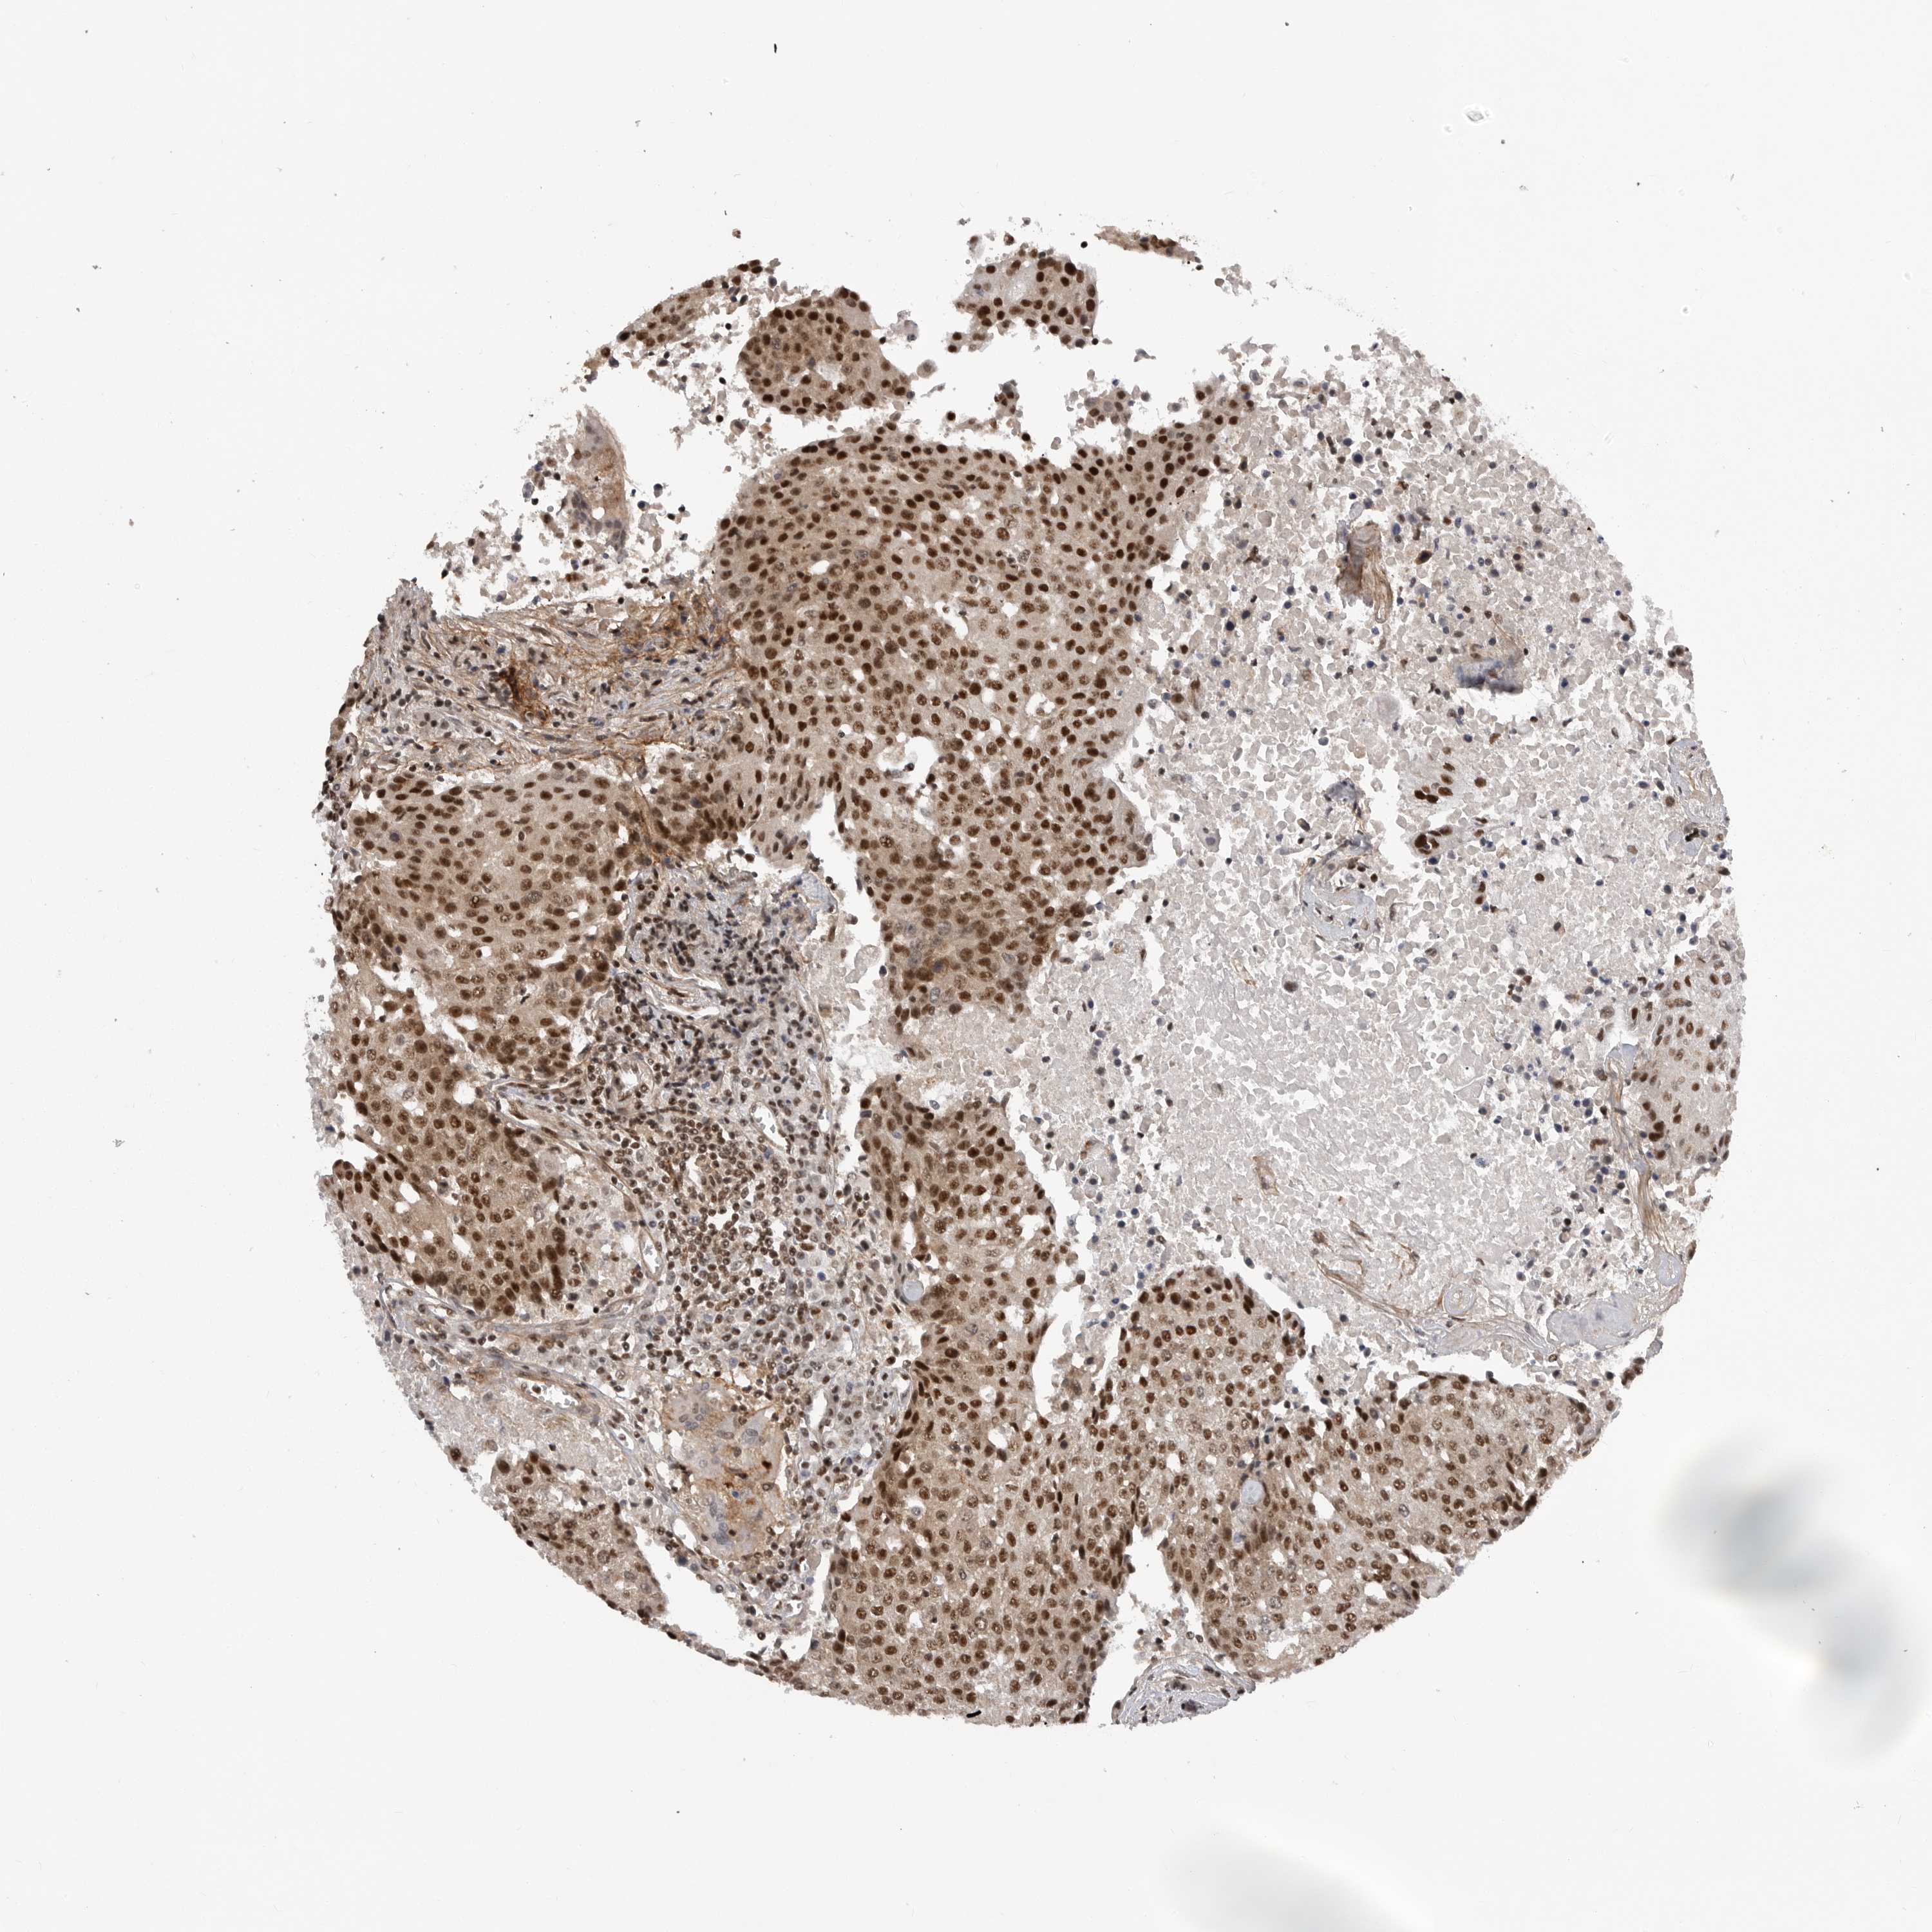

UROTHELIAL CANCER - Protein expressioni

A mouse-over function shows sample information and annotation data. Click on an image to view it in a full screen mode. Samples can be filtered based on level of antibody staining by selecting one or several of the following categories: high, medium, low and not detected. The assay and annotation is described here.

Note that samples used for immunohistochemistry by the Human Protein Atlas do not correspond to samples in the TCGA dataset.

Antibody stainingi

Antibody staining in the annotated cell types in the current human tissue is reported as not detected, low, medium, or high, based on conventional immunohistochemistry profiling in selected tissues. This score is based on the combination of the staining intensity and fraction of stained cells.

Each image is clickable and will lead to virtual microscopy that enables deeper exploration of all samples and also displays staining intensity scores, fraction scores and subcellular localization as well as patient and tissue information for each sample.

Antibody HPA027406

Antibody HPA027417

Antibody HPA027452

Urothelial carcinoma, Low grade

Urothelial carcinoma, High grade